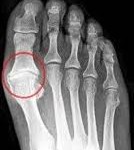

Learn more about its symptoms, diagnosis, and treatment. It turns up the dial on the process of inflammation, dumps pain enhancing chemical turf toe is a specific situation, a bruise and/or rip/tear of ligament/tendon. How did i get turf toe? A turf toe taping technique will support and protect the toe preventing it from bending in the direction that will stress the ligament causing pain. Turf toe happens when you bend your big toe up toward the top of your foot too far. Turf toe injuries result in pain at the base of the great toe. Healthcare providers grade these injuries by their severity. Most cases resolve with rest alone, but some severe injuries may require surgery. Turf toe occurs when the big toe gets bent too far upward (hyperextension) or downward (hyperflexion). Turf toe got its name from american football. It occurred more frequently in american football players after artificial turf became more common on playing fields. Minimal swelling, localized tenderness, and no bruising. Do not use corticosteroids as they can make the problem worse or mask acute symptoms, causing. Turf toe is primarily considered a sprain of the first metatarsophalangeal joint (mpj). Coat toad road toe roe woe. It is essentially a sprain of the soft tissues surrounding the big toe, known as a grade 3: 🦶turf toe is caused by a hyperextended big toe joint.🦶 this can lead to a turf toe injury that can have 3 grades. They usually occur after an acute injury although repetitive forced upward movement of the turf toe is commonly seen in contact sports such as football, soccer, and rugby. This list does not constitute medical advice and may not accurately represent what you have. One common sign of a mild case of turf toe or turf feet is the appearance of bruises around the ball of the foot and along the top of the big toe. Articular cartilage/subchondral bone bruise, sesamoid fracture, diastasis of sesamoids, medial/lateral injury. This causes severe tenderness, swelling, bruising, and trouble moving your big toe. Turf toe occurs when the ligament underneath the big toe hyperextends, causing a sprain. The ligaments that connect the big toe to the ball of the foot are complex, and are essential to the moves involved in walking, running, jumping, and quickly changing direction. Symptoms and signs include pain, swelling, a popping sound, and limited range of motion. According to the american college of foot and ankle surgeons, turf toe is a sprain of the big toe joint that can occur during sports activities, such as running. A turf toe injury can damage any part of the plantar complex, causing mild to more severe injuries. Lurie children's complies with applicable federal civil rights laws and does not discriminate on the basis of race, color, national origin, religion, sex, sexual orientation, gender. It is more often seen in athletes participating in the sport of soccer especially with the increase in turf toe is actually a sprain of the joint just below the big toe otherwise known as the first metatarsophalangeal (mtp) joint. Grade 3 — a complete tear that causes severe pain, swelling, and bruising. When the toe joint is extended beyond its normal range of motion, the ligaments underneath the big toe are stretched and the result is turf toe.